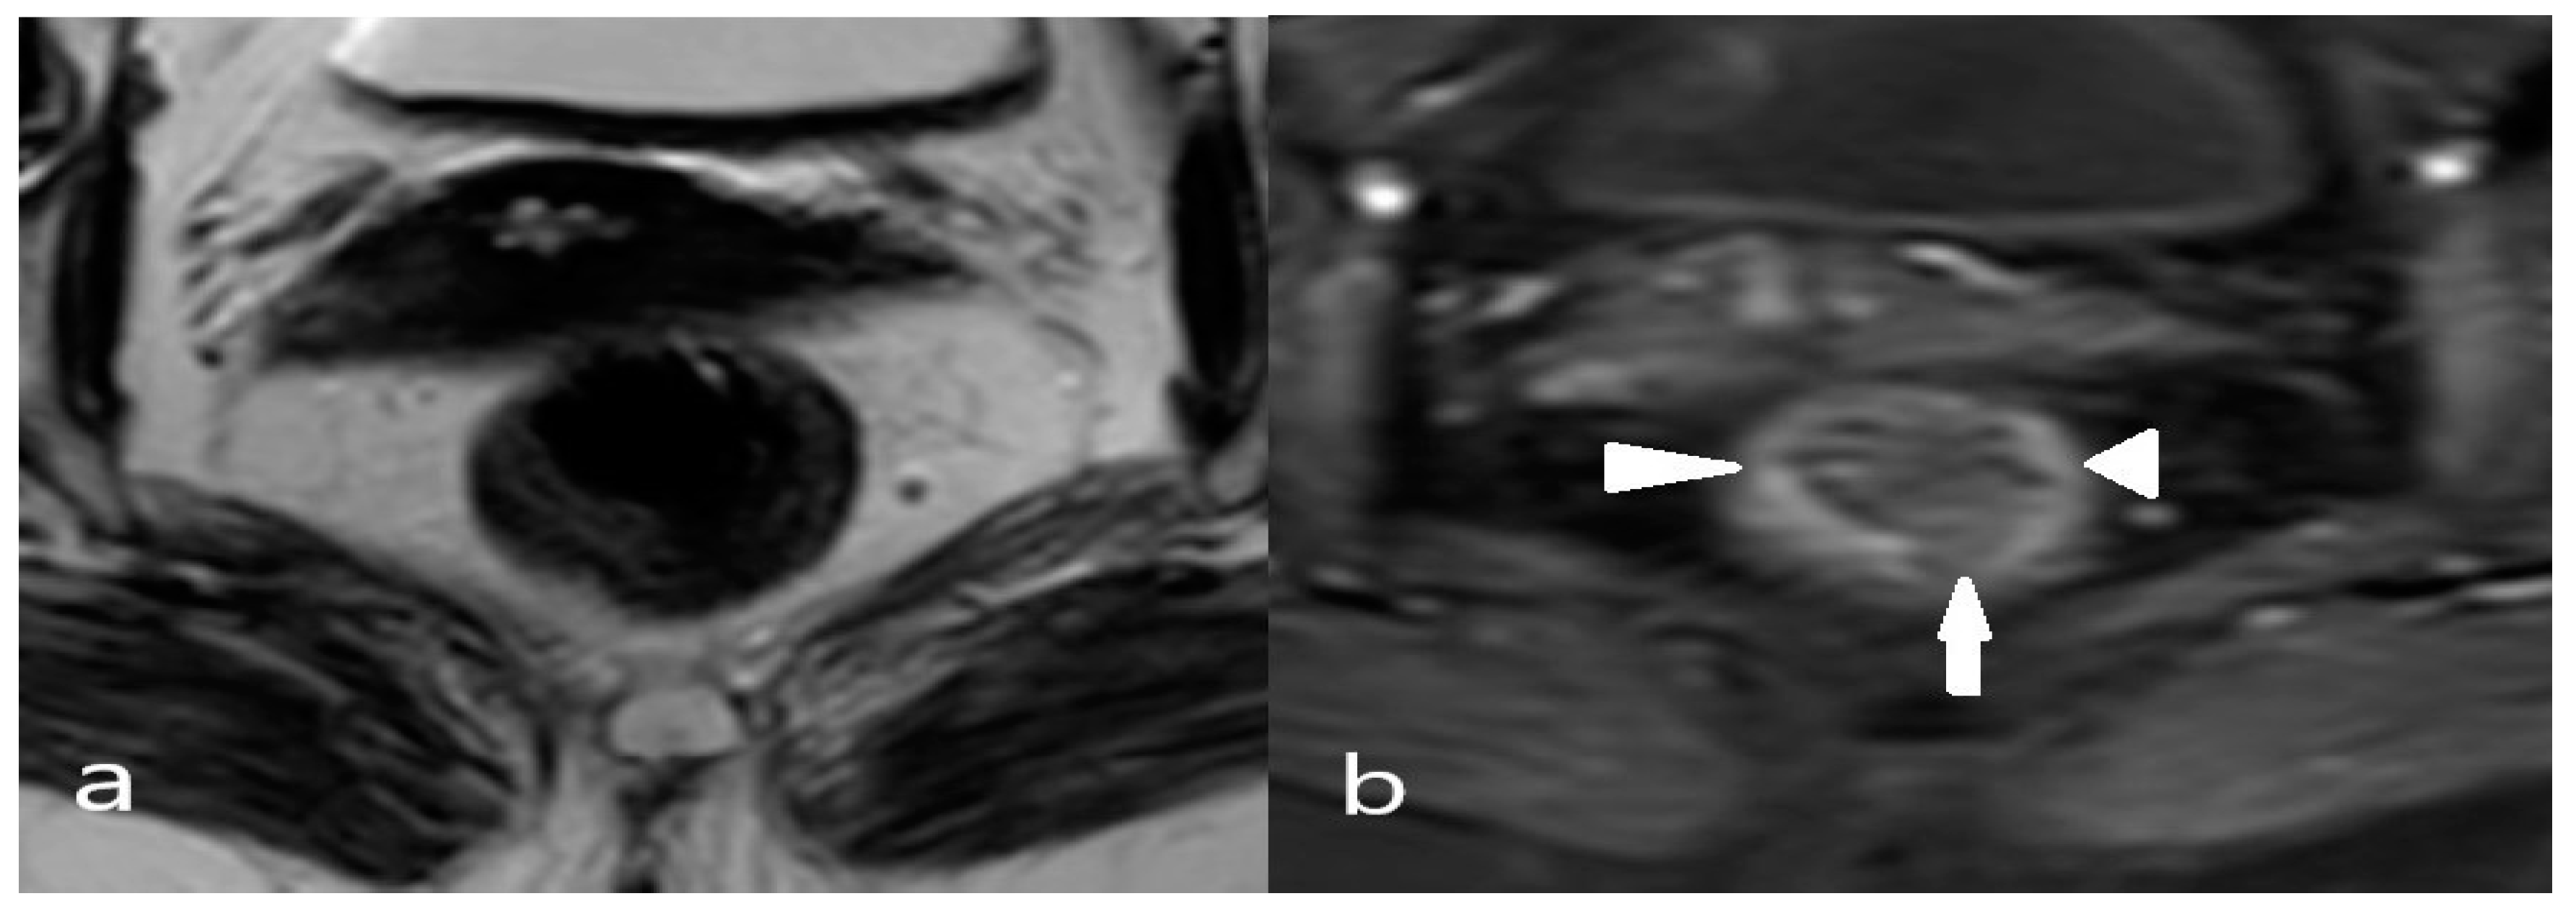

2.4. MRI Evaluation

2.5. Anatomical Classification of Lateral Lymph Nodes and Classification of Pathological Lymph Nodes Based on Size